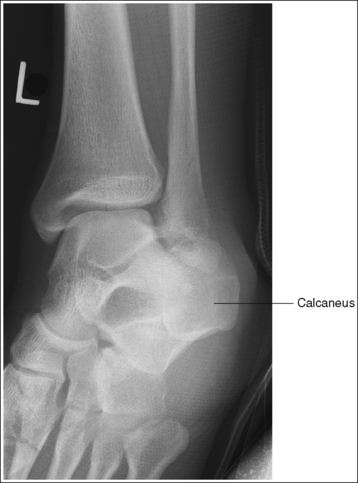

See Figure 6-46 and Box 6-10.

The ankle is demonstrated in an AP projection. The medial mortise (tibiotalar articulation) is open, and the distal tibia and talus are superimposed over the distal fibula by a small amount (0.125 inch [3 mm]), closing the lateral mortise (fibulotalar articulation).